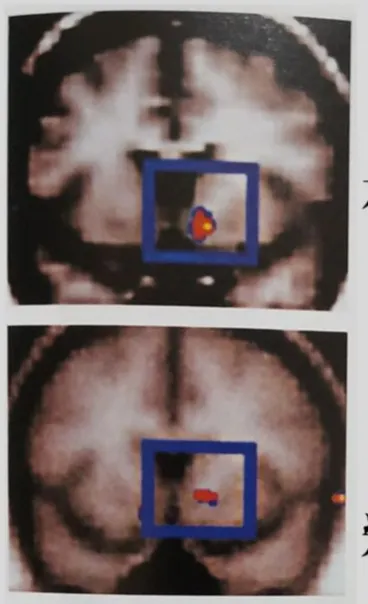

懂了腦袋很難控制,就能説説這張投影片了,大叔沒有醫學背景,就盡力講解一下吧。下圖是使用核磁共振攝影( MRI )之類儀器拍下的照片,可以觀察人在進行特定行為時,大腦是那個部位有在活躍,大叔放大給你看清楚。

照片是觀察多個實驗對象,安排他們進行不同活動時,記錄下來腦部活躍區塊的影像,也就是藍色框框裡的紅色區塊。

一張是讓實驗對象,想到能賺大錢的腦部活躍區。另一張則是讓有毒癮的實驗對象,想像即將再注射毒品前的腦部活躍區塊。是的,同一個部位。你覺得單憑本身意志力,想要克服毒癮(賺大錢)的念頭簡單嗎?